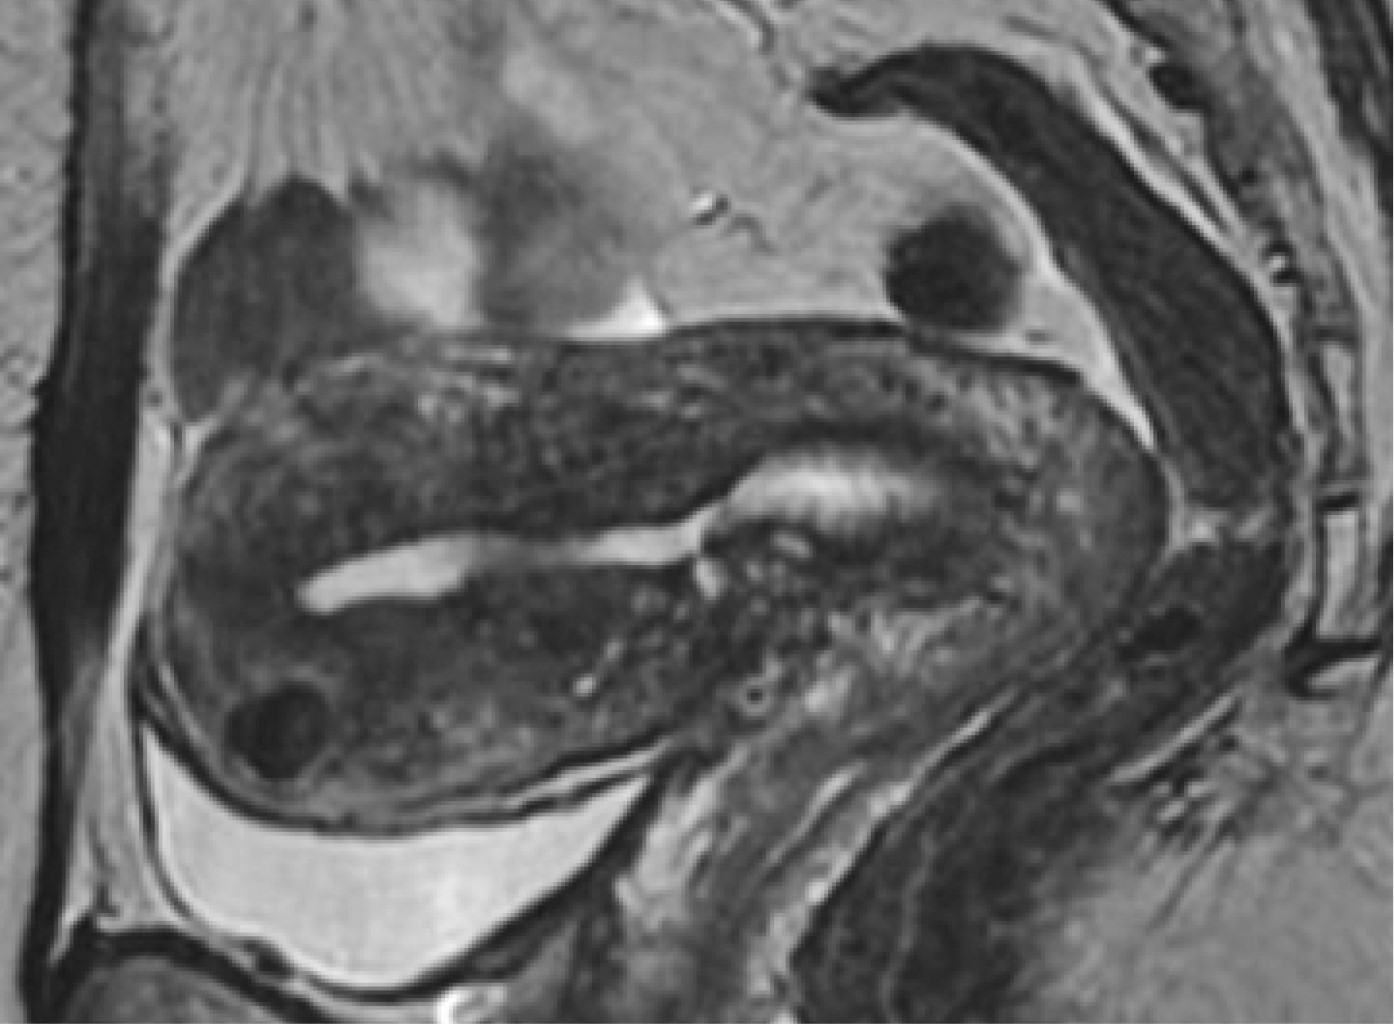

Para el uso de ultrasonido se recomienda un abordaje transvaginal, encontrando infiltración endometrial: con estriaciones ecogénicas y nódulos, quistes miometriales y divertículos "lollipop"; así como proliferación de músculo suave, ya sea de tipo focal o difuso con bordes en el miometrio. En cuanto a la vascularidad, mediante ultrasonido Doppler se observa aumento de la angiogénesis con vasos tortuosos. La mayor sensibilidad en el diagnóstico se logra con el uso de la resonancia magnética, en la que los hallazgos son similares a los observados en el ultrasonido;8 dentro de estas observaciones se entiende lo siguiente:9 en las imágenes T2 se observa alargamiento uterino con regiones más definidas y de baja intensidad con hiperplasia del músculo liso (zona de unión de más de 12 mm), quistes miometriales hiperintensos que reflejan regiones del tejido miometrial ectópico; con posible señal T1 intrínseca incrementada o con mayor sensibilidad para focos hemorrágicos. No existe recomendación de mejora con el medio de contraste, ya que no permite valorar o identificar la vascularización de la zona (Figura 2).

Figura 2